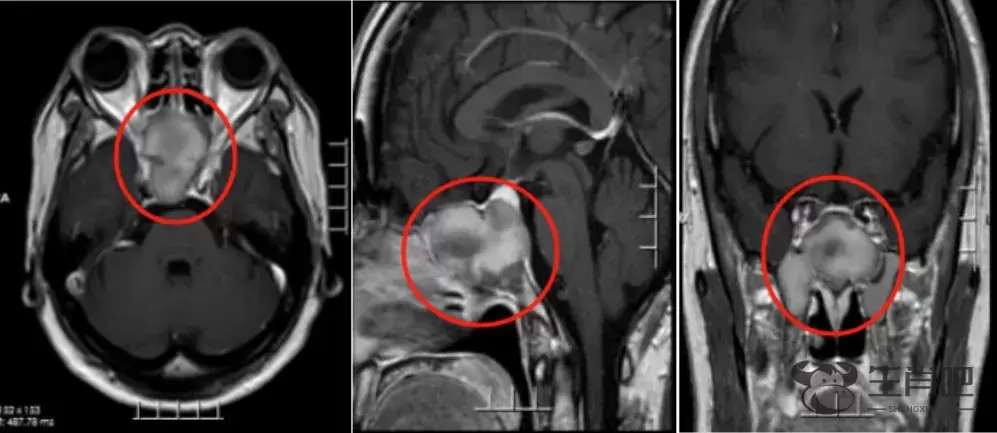

医生经过检查后发现患者蝶窦异常扩大,内含大量均匀异常信号影,考虑粘液囊肿或真菌感染的可能。邻近右侧眠尖区受挤压,蝶鞍及垂体受压上抬。蝶窦占位诊断明确,考虑行内镜下经鼻蝶窦占位切除术。

医生在为其做了手术,根据术后病理提示:(鞍底、蝶窦鞍底、蝶窦占位)符合真菌感染,确诊为曲霉菌感染。